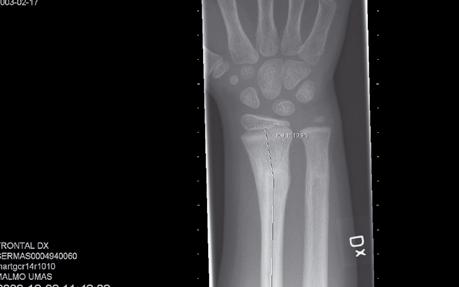

På onsdagsmorgonen gick Yngvar Krukhaug, Bergen, på ett didaktiskt sätt igenom eviden sen för olika behandlingsstrategier av distala radiusfrakturer. ”Take home message” blev att de data vi grundar våra beslut på generellt är av undermålig kvalité, att gipsbehandling kan användas i 80 % av fallen och att det nu finns evidens för användning av volar plattfixation vid instabila AO C1 och C2 frakturer. Vid mer splittrade frakturer finns inga data som visar att volar platta är bättre än externfixation, nå got som ytterligare diskuterades vid efterföl jande symposium om indikationer för vinkel stabila plattor med Ingvar Allvin, Örebro, som moderator.